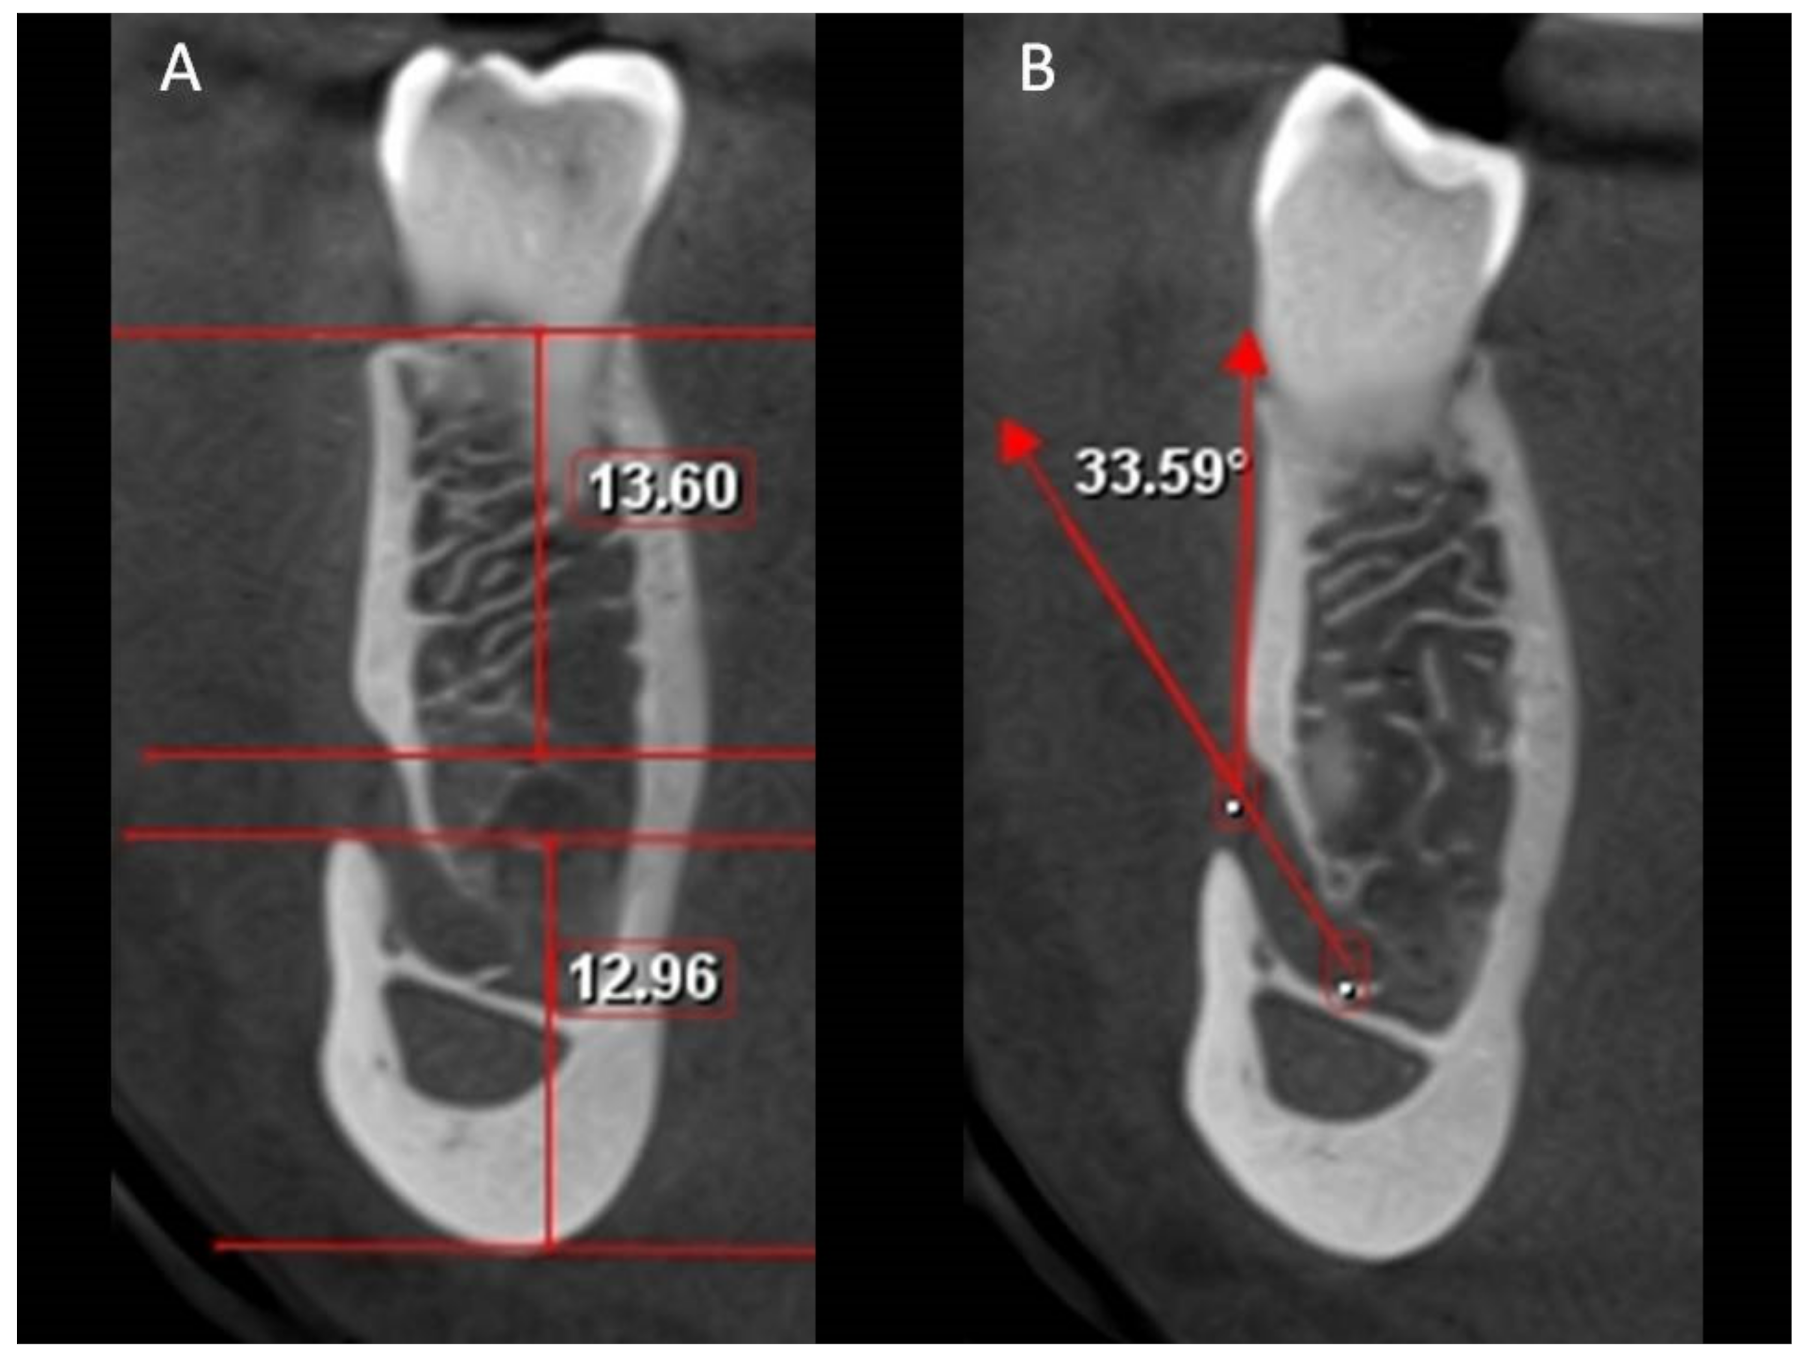

| Sagittal view | ||||||||||

| Height of MF | 1.66 | 5.44 | 3.14 | 0.72 | 1.06 | 4.48 | 1.64 | 0.70 | 4.463 | 0.000 * |

| Length of MF | 1.60 | 6.40 | 3.57 | 0.96 | 1.12 | 5.65 | 1.19 | 0.78 | 5.358 | 0.000 * |

| Coronal view | ||||||||||

| Angulations of MeC | 17.51 | 87.39 | 46.67 | 14.82 | 1.06 | 4.48 | 42.38 | 13.82 | 2.616 | 0.009 * |

| Distance from MF to crestal bone | 8.96 | 20.81 | 14.21 | 2.46 | 1.12 | 5.65 | 13.48 | 2.20 | 2.759 | 0.006 * |

| Distance from MF to lower border of mandible | 9.28 | 19.36 | 13.58 | 1.78 | 1.06 | 4.48 | 12.06 | 1.35 | 8.231 | 0.000 * |